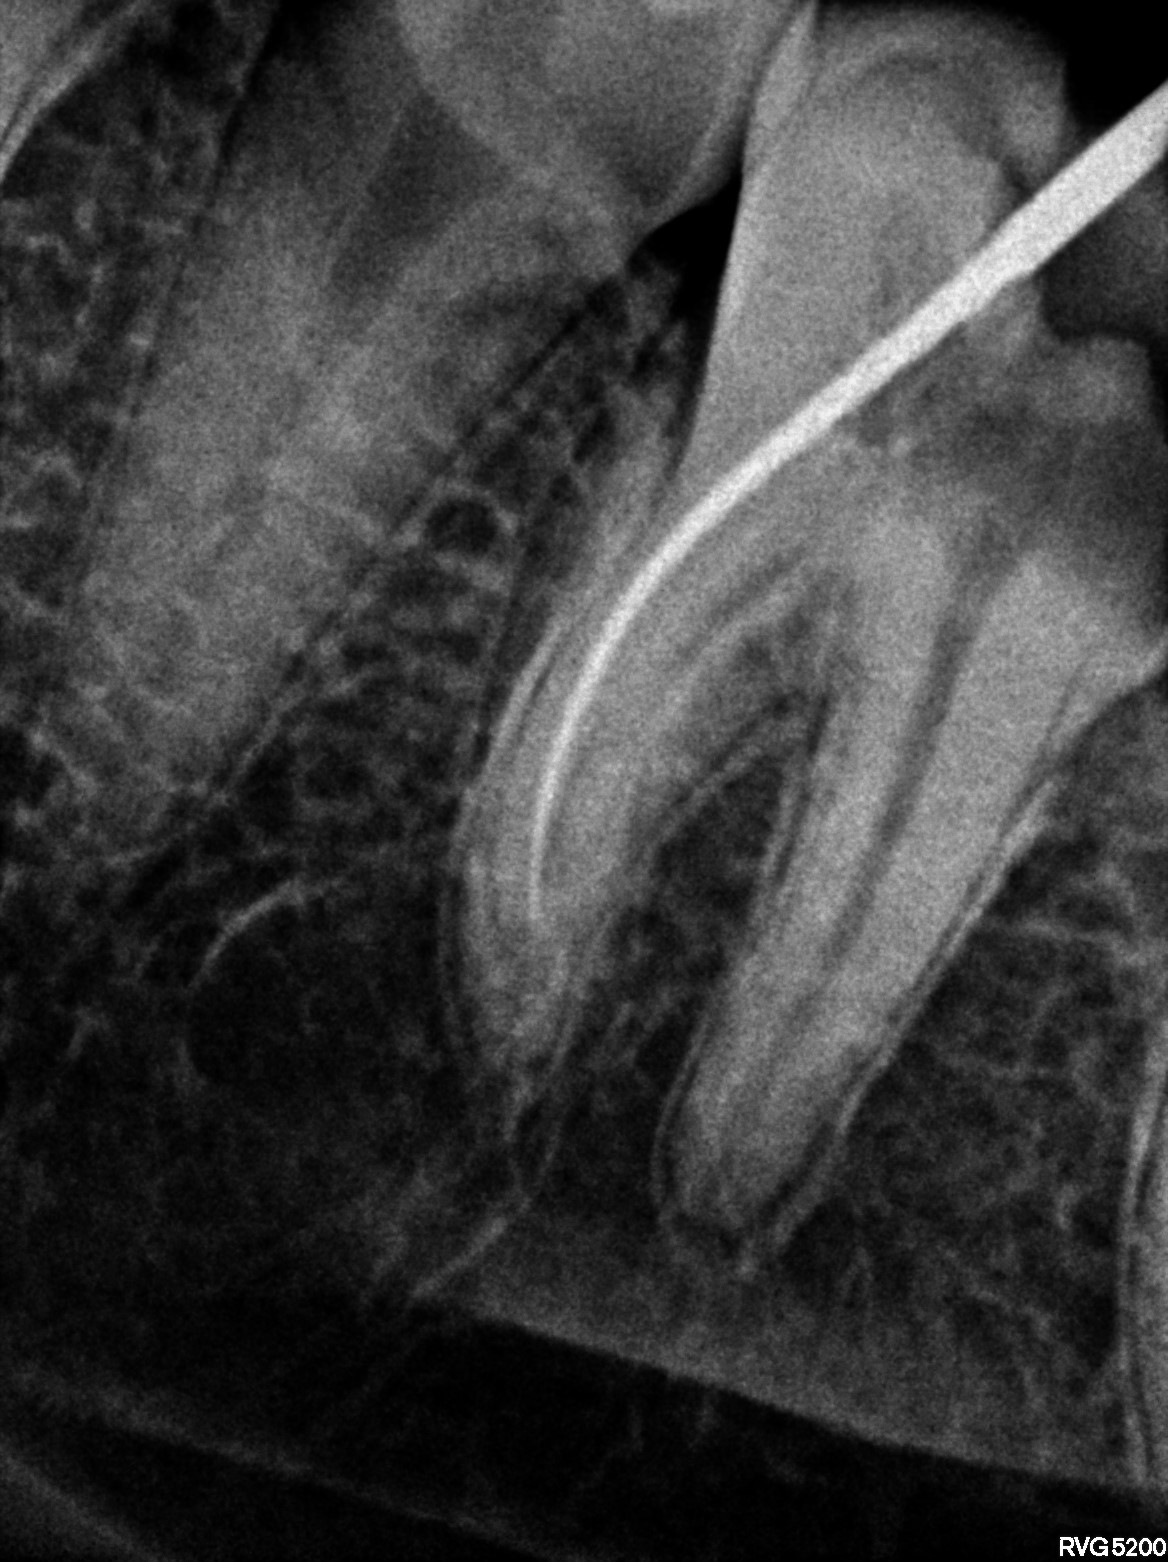

Dental Radiographs FHIR: DocumentReference · LOINC 24641-7

xray_1772782008_2.jpg

24641-7